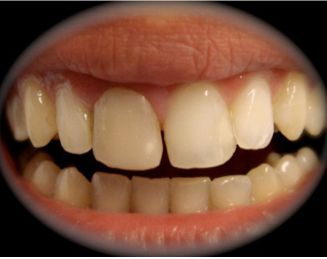

Paciente de sexo femenino, de 34 años de edad, que presenta un tratamiento de conducto deficiente en la pieza 11, con restauración de resina de larga data y con una fístula a punto de partida de gangrena pulpar.

Al estudio RX se aprecia un conducto amplio, sobre todo en su tercio cervical con paredes bastante delgadas. (Fig. 1)